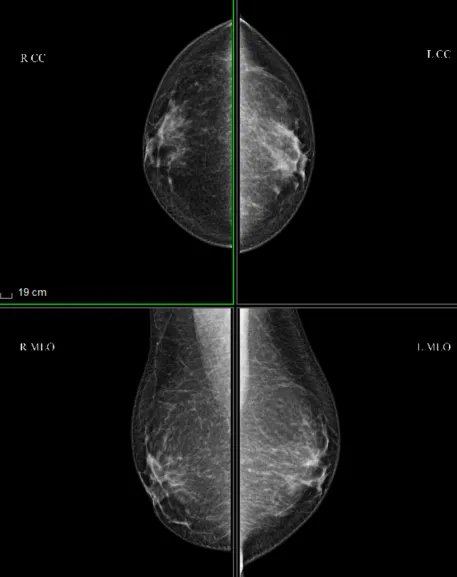

我院的乳腺钼靶机

我院配备的乳腺钼靶机,具有高清晰、高分辨率及伪彩功能,能极大提高乳腺疾病的正确诊断率。它能清晰显示乳腺各层组织,可以发现乳腺增生、各种良恶性肿瘤,可观察到小于0.1毫米的微小钙化点及钙化簇,能对彩超无法辨别的乳腺病变钙化点进行准确判断与鉴别。